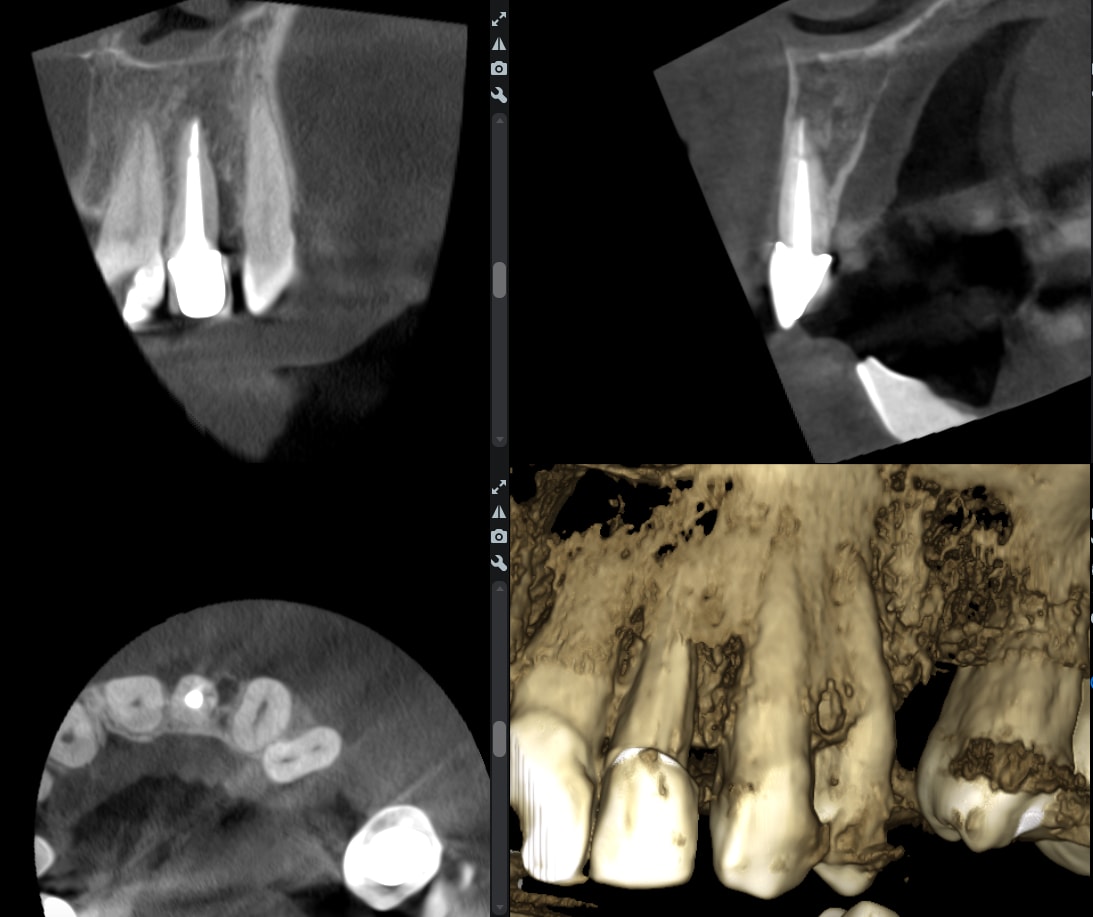

Marrant parce que cette fêlure sur 22, on ne la voit pas du tout sur la rétro, mais très bien sur la reconstruction 3D du CBCT

Jwjbelah9gpo9q1h8cqdm9j3kbi5 - Eugenol

Pevaeb5p7eph9oqexipq9lo1cuwa - Eugenol

Tu ne peux absolument pas conclure que ce qu’on voit ici est une fêlure. C’est plus vraisemblablement un artefact du au matériau canalaire.

Indépendamment de la remarque de dentarue (les reconstitutions 3D c'est dégueulasse et c'est compliqué de conclure quelque chose dessus. Seules les coupes sont fiables), c'est exactement ce que je disais: dans ton cas ta 2D ne montrait rien à cause du tenon. Mais si on en croit ton interprétation de la 3D, il y a déplacement des fragments et un espace visible en 3D, c'est plus une fracture qu'une fêlure à mon sens. Il faudrait peut être définir ces termes, quelqu'un sait s'il existe une vraie définition scientifique?

Il n'y a qu'en modifiant les niveaux sur la recoonstruction 3D qu'on la met en évidence.

J'appelerais cela une fracture bien contenue..

5ff2w2nwnimf68wydp5d6qtlkgwo - Eugenol

Mouais, ou un artefact comme dit par dentarue. La reconstitution 3D n'est à ma connaissance prévue que pour une visualisation d'ensemble, pas un diagnostic précis sur une zone limitée. La reconstruction extrapole des trucs entre les plans de coupe et n'est absolument pas fiable. Il n'y a qu'à voir tous les espèces de grumeaux qu'on voit systématiquement partout sur les images.

Une image comme ça moi je n'en conclus rien, je me fie aux symptômes (il semble quand même y avoir une perte osseuse vestibulaire bien plus marquée que sur les voisines qui pourrait signer la fracture) et je dépose pour contrôler visuellement avant de décider d'avulser.

La 3d apporte beaucoup plus de renseignements dans le mouvement, comme une échographie, ça permet de se représenter un volume en 3d.

Si on se contente de regarder des coupes on est en 2d.